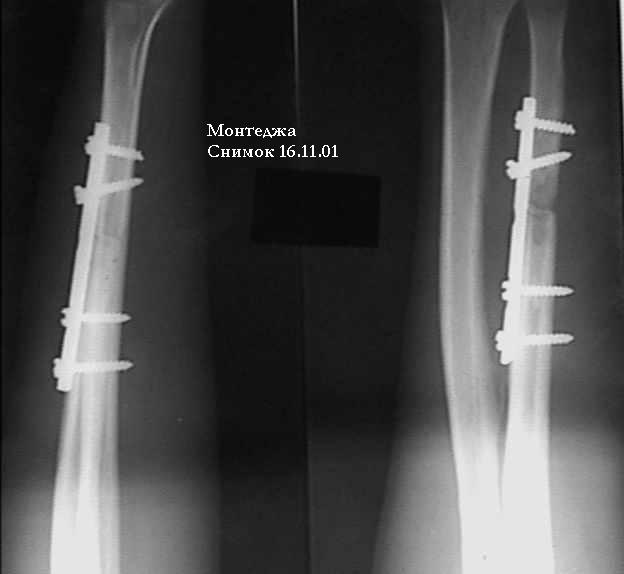

У больного травма в октябре 2001. Перелом Монтеджа разгибательный.Проведена операция металлостеосинтез пластиной, винтами локтевой кости. Вывих головки лучевой кости не диагностирован. В конце февраля 2002 г снята гипсовая повязка. Имеется ограничение сгибания до 115 градусов. Больной обратился в наше лечебное учреждение 07.02.02. Мы предложили ему оперативное лечение. Планируем провести резекцию головки лучевой кости. Есть мнение попытаться вправить головку лучевой кости, провести пластику кольцевидной связки, фиксисировать головку лучевой кости трансартикулярно спицей. Но боюсь, что в момент остеосинтеза была укорочена локтевая кость, поэтому необходимо будет провести резкцию в области диафиза лучевой кости, а затем провести остеосинтез лучевой кости. Рентгенограммы:

1; 2; 3; 4